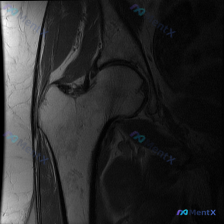

整理了一份肩部MRI病例讨论材料,医生的核心问题是排查盂唇病变,但看影像发现了一些矛盾点。先放MRI T2序列冠状位的分析: 1. 骨性结构:肱骨头、肩峰及锁骨远端轮廓尚可,未见骨折线或骨髓水肿 2. 肌腱与肩袖:冈上肌腱在肱骨大结节止点处形态异常,连续性中断,T2高信号 3. 关节与滑囊:肩峰下-...

最近整理了一份肩部MRI的病例讨论材料,患者主要问题是肩部疼痛,但问题明确指向"盂唇病变"范畴。先看T2冠状位图像的关键发现: 1. 冈上肌腱在肱骨大结节止点处有显著高信号,连续性可能中断 2. 肩峰下-三角肌下滑囊有明显的高信号积液 3. 关节盂唇区域信号存在改变 大家觉得这个病例更符合哪种诊断?...

整理了一个肩关节MRI-T2序列冠状位的病例讨论材料,医生提问关注盂唇病变,但影像最突出的是冈上肌腱全层撕裂。这份病例的核心疑问点和影像发现存在一定不匹配,大家第一眼怎么看?